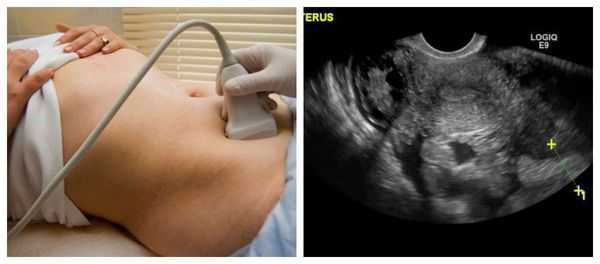

Визуализация включает трансвагинальное ультразвуковое исследование, в случае если:

Подозрение на структурное поражение (на основании анамнеза или обследования)

Локальное утолщение эндометрия, обнаруженное на УЗИ, может потребовать гистероскопии или соногистерографии для выявления небольших внутриматочных образований (например, полип эндометрия, миома).

- состояние эндометрия и яичников на основе данных УЗИ органов малого таза (с применением ректального датчика у девственниц или влагалищного - у девушек, живущих половой жизнью). Эхограмма яичников при ювенильных маточных кровотечениях показывает увеличение объема яичников в межменструальный период

- УЗИ контроль овуляции (с целью визуализации атрезии или персистенции фолликула, зрелого фолликула, овуляции, образования желтого тела)

- Ультразвуковое исследование. С помощью УЗИ тазовых органов визуализируются матка, придатки, обнаруживаются объемные новообразования, признаки диффузного разрастания эндометрия, другие причины, вызывающие возникновение кровянистых выделений без запаха или с запахом. В затруднительных ситуациях, когда врач не может верифицировать диагноз, прибегают к диагностической лапароскопии.

Необходимо проведение УЗИ органов малого таза. При его выполнении редко можно увидеть изменения в яичнике, но иногда обнаруживаются косвенные признаки патологии — небольшое скопление жидкости позади матки.

При этой форме апоплексии яичника обязательно проведение УЗИ, при котором определяется большое количество свободной жидкости в брюшной полости со структурами неправильной формы (кровяными сгустками).